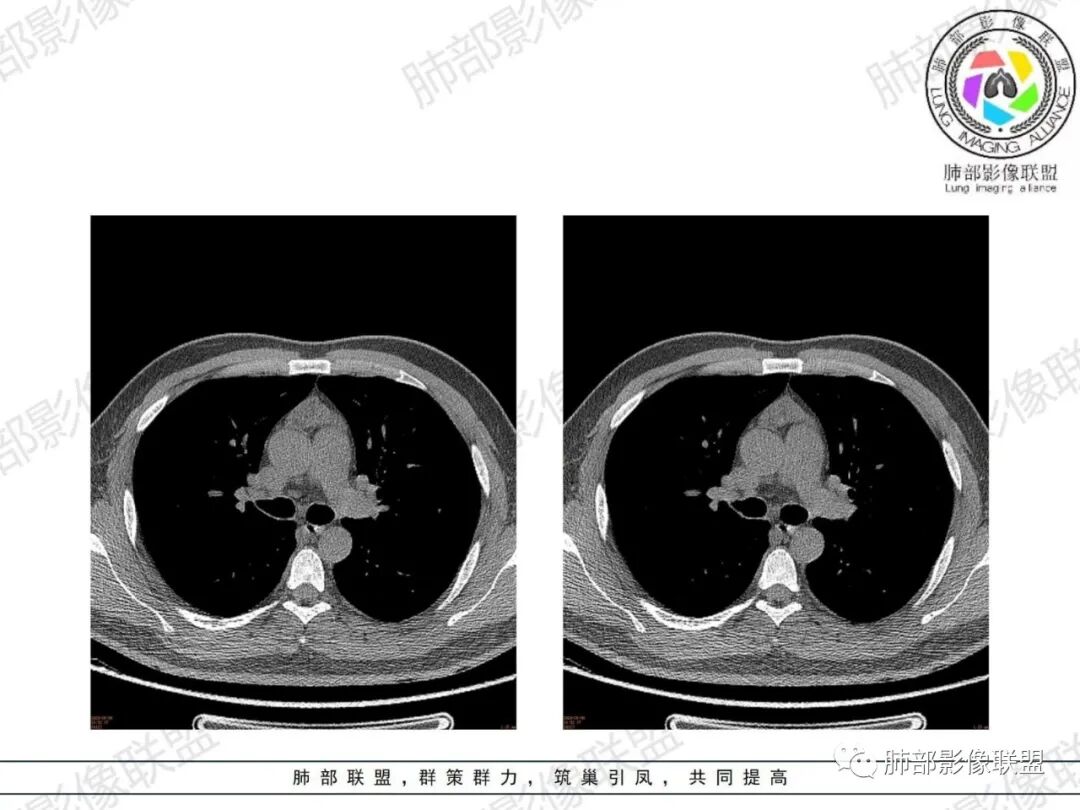

胸腺增生CT表现

体积、形态:

弥漫性增大,两缘对称,质地柔软,部分淋巴性胸腺增生的大小正常;形态保持其正常形态,呈类圆形、梨形,边缘光滑,可呈浅分叶

密度:

密度均匀,呈肌性密度,偶见细小钙化,其内有脂肪浸润样密度影

强化:

轻度或无强化

与周围结构关系:

与周围大血管、胸骨等周围组织结构分界清楚,无淋巴结肿大、胸膜及心包受累。

胸腺瘤好发于成年,肿块呈结节状或分叶状,质地较硬,并向一侧或两侧突出,或侵及心脏大血管间隙,分界可不清楚,恶性者可伴胸膜、心包膜受累及淋巴结转移;增强扫描胸腺瘤多均匀或明显强化,胸腺增生略强化或强化不明显;若胸腺增生表现为结节或肿块样,CT与胸腺瘤难鉴别,可以用MRI化学位移成像对鉴别两者有帮助,正常胸腺和胸腺增生因弥漫脂肪浸润在反相位上呈衰减信号。无论是胸腺瘤还是胸腺增生都主张积极手术切除。

1、年轻男性,双下肌乏力,胸部CT提示前纵隔胸腺区病变,应当怀疑胸腺增生或胸腺瘤导致的重症肌无力。

2、前纵隔梨形软组织密度影,与正常胸腺形态一致,为胸腺弥漫性增大,两缘匀称,质地柔软,未见明显膨隆,其内可见脂肪浸润影,与周围结构分界清楚,再加上病人年龄,需要高度提示胸腺增生(淋巴滤泡样增生型)。胸腺瘤一般无脂肪浸润,质地较硬,呈结节或肿块状,且发病年龄较大。B2B3型肿块边界不清,可侵犯临近组织脏器,B3可胸膜转移,胸腺癌可引起纵隔淋巴结及远处转移。